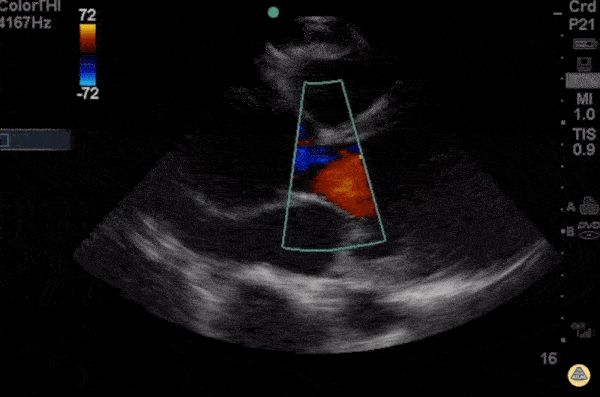

This is a parasternal long axis view of a young patient presenting with 3 days of progressive dyspnea on exertion. He had no chest pain, a normal chest x-ray and and ECG with sinus tachycardia. Beside ultrasound got him to the OR in under 1 hour. The rule of thirds states that in parasternal long, the right ventricular outflow tract, the aortic root, and left atrium should roughly be equal size. Any disparity between these can hint at pathology. In this case, the patient had severe and sudden aortic regurgitation and widening of the aortic root consistent with aortic dissection. - Michael Macias, EM Resident Physician PGY-4, Northwestern University